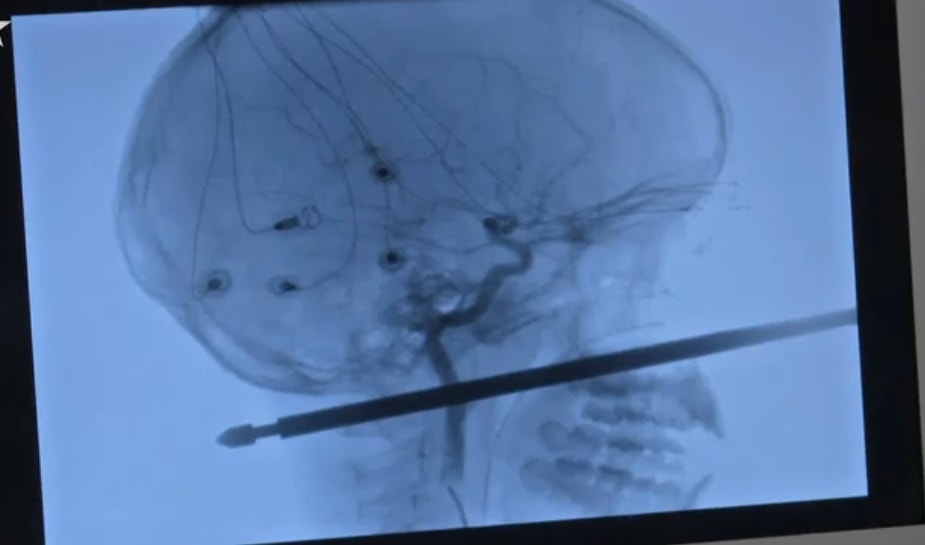

KANSAS CITY – Stava giocando nella sua casa sull’albero quando è stato attaccato da alcune vespe ed...